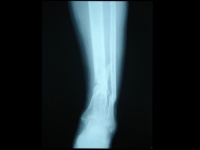

胫腓骨骨折

X线正位片应包括胫腓骨全长,以免漏诊。X线可见骨折线、碎骨片、断端移位等。

x线检查在胫腓骨骨折中用于诊断、估计骨折愈合的程度、发现骨折的并发症及、做必要的鉴别诊断。

在临床上,一旦怀疑有胫腓骨骨折,就要拍摄小腿正侧位的X线片,照片质量要求较高,除了能发现明显骨折外,对怀疑的线状裂纹也要确定,因为线状骨折也影响愈后和治疗,如行内固定,其稳定性要把线状骨折的因素考虑在内。

在晚期估计其愈合的程度时,有时要拍摄透过骨折端的斜位片。复位后的x线片最好包括膝、踝两个关节,以确定这两个关节轴线在平行的位置,防止晚期因膝、踝关节面的不平行而造成的并发症。原则上拍小腿x线片时要包括胫腓骨的全长。以防止低位胫骨骨折,合并有高位的腓骨骨折发生漏诊。

在骨的x线描述上,首先确定骨折的部位,在上l/3、中l/3或下1/3。再确定骨折类型是横断、斜行或螺旋型骨折,骨折有无粉碎,以及是否多段。侧方移位严重则愈合很难。×线片上不易确定上下骨折段的旋转移位,要从临床上来判断和纠正。